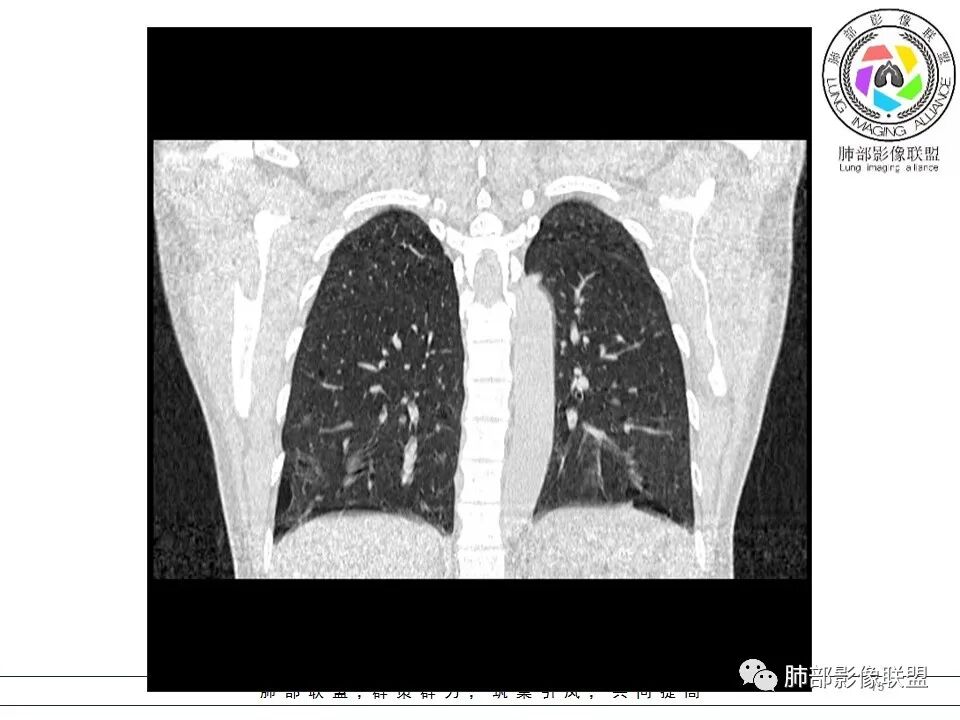

青年女性,ct双肺多发囊性病变,形态不规则,左肺舌段,肋隔角受累,下叶多,母亲有类似病史,考虑BHD,鉴别LAM。

青年女性,双肺多发囊性病变,形态不规则,下叶多且大,母亲有类似病史,考虑BHD。多发肺大泡+肾脏肿瘤+皮肤纤维囊腺瘤=BHD

双肺多发大小不等肺气囊,边界清楚,薄壁,壁光滑,以胸膜下分布为主,肋膈角也有受累,临床年轻女性,考虑LAM(年轻女性好发),鉴别BHD(需要询问家族史),LCH(吸烟,及肋膈角不受累)。

双下肺为主多发怪异囊,与胸膜关系密切。青年女性,可疑家族史。考虑BHD。建议皮肤+肾脏检查。确诊:基因检测。

青年女性,两肺多发薄壁囊肿影,两下肺明显,母亲类似病史,考虑BHD,LAM

青年女性,双肺胸膜下多发大小不等、多形态囊腔,薄壁,有肺大泡家族史,考虑BHD,鉴别LAM,建议结合肾脏、皮肤检查

青年女性,双肺胸膜下多发大小不等、多形态囊腔,肺大疱,有肺大泡家族史,考虑BHD,鉴别LAM,建议基因检测

LAM?年龄、性别符合,囊形态符合,但是这么大囊的好像不多见,而且分布区域下肺为主的不多,没有结节,不是首选,但是不能排除

Birt-Hogg-Dubé综合征:影像符合,家族史符合

BHD主要影像表现特征:    1、两肺内肺囊肿:80%以上的BHD患者会出现肺内囊肿,且倾向于基底部近胸膜下分布,特别是纵膈侧肺膜下,囊肿形状不规则、囊肿可大可小,肺内囊肿多毗邻肺下动脉或静脉近端,胸部CT上囊肿分布和特点对诊断有提示意义。    2、继发自发性气胸:BHD患者发生气胸风险是正常人的5倍,BHD患者的气胸发生率约为 1/4,气胸复发率则高达59%。   3、肾肿瘤:(常为双侧性、倾向于嫌色细胞组织学亚型)   4、皮肤表现(为面、颈部纤维性毛囊瘤、毛盘瘤)